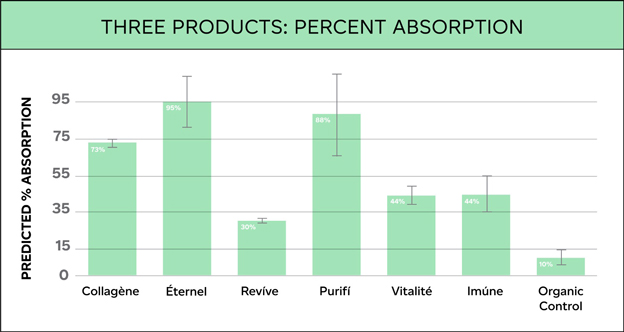

Predicted cellular absorption and bioavailability percentages of THREE’s products are shown in Figure 1 below. Actual numbers are as follows: Éternel = 95%, Purifí = 88%, Collagène = 73%, Vitalité = 44%, Imúne = 44%, Revíve = 30%, and curcumin (Organic Control) = 10.

The correct way to analyze the data in Figure 1 is to compare the percent absorption of each product to the organic control—and not between products.

When looked in this way, Revíve, with a cellular absorption percentage of 30, is 3X more bioavailable than curcumin (organic control), which represents a standard organic molecule and served as the control in the experiment. Éternel is 9.5X more bioavailable than curcumin. The significant increases in cellular absorption and bioavailability in THREE’s products versus a standard molecule like curcumin (organic control) is due to the Cellular Absorption Technologies used in THREE’s products that help to shuttle the ingredients in the formulas across the cellular membrane and into the cell at a much higher concentration.

A Caco-2 in-vitro cellular absorption assay was used to calculate percent absorption and bioavailability of THREE’s products.

The data found that THREE’s products, due to the Cellular Absorption Technologies used, are between 3 and 9.5 times more absorbable than a standard organic molecule using no delivery technology. Increased cellular absorption and bioavailability should equate to increased product efficacy.